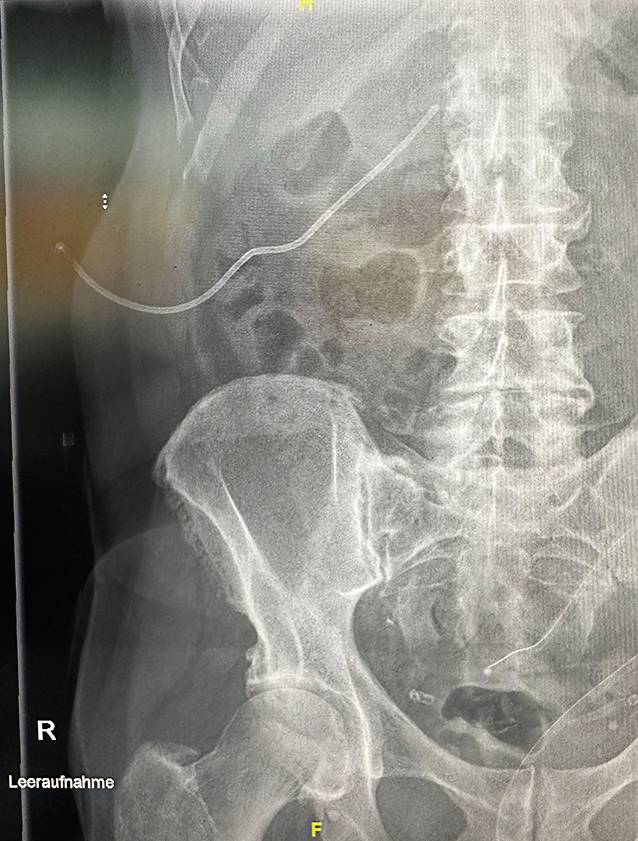

Die dOFD wurde mit einer Trelumina Sonde (Freka® Trelumina, Fresenius SE & Co. KGaA, Bad Homburg, Deutschland) und der offenporigen Drainagefolie (Suprasorb® CNP Drainagefolie, Lohmann & Rauscher International GmbH & Co. KG, Rengsdorf, Deutschland) hergestellt. Als Drainageelement wurde der gastrale Ableitschenkel der Sonde über eine Länge von insgesamt 25 cm mit der dünnen Folie ummantelt. Zur Fixierung der Drainagefolie verwendeten wir eine Fadenumwickelung mit Polyesterfaden (Mersilene®, Ethicon Deutschland Johnson & Johnson, Norderstedt, Deutschland). Der Belüftungsschenkel der Sonde wurde mit einer Klemme verschlossen, er wird nicht benötigt (Abb. 2).

Abb. 2

Doppellumige offenporige Foliendrainage (dOFD): Drainageelement (DE) mit folienummanteltem gastralem Schenkel und Ernährungssonde (iT)

Die dOFD hat einen Durchmesser von nur 6 mm. Die transnasale Einführung erfolgte unter endoskopischer Sicht in gleicher Technik wie bei einer gastroduodenalen Ableitsonde. Der intestinale Ernährungsschenkel der dOFD wurde endoskopisch entlang des Pylorus in das Duodenum vorgeschoben und die dOFD mit dem offenporigen Folienabschnitt durch weiteres Vorschieben tief im Duodenum, die Defektregion überdeckend, platziert (Abb. 3).

Abb. 3

Platzierungsmanöver der dOFD. Ernährungssonde (iT), Übergang zum folienummantelten Abschnitt (DE), übernähter Perforationsdefekt (P) des Nephrostomiekatheters mit perifokalem Ödem und lokalen Entzündungszeichen